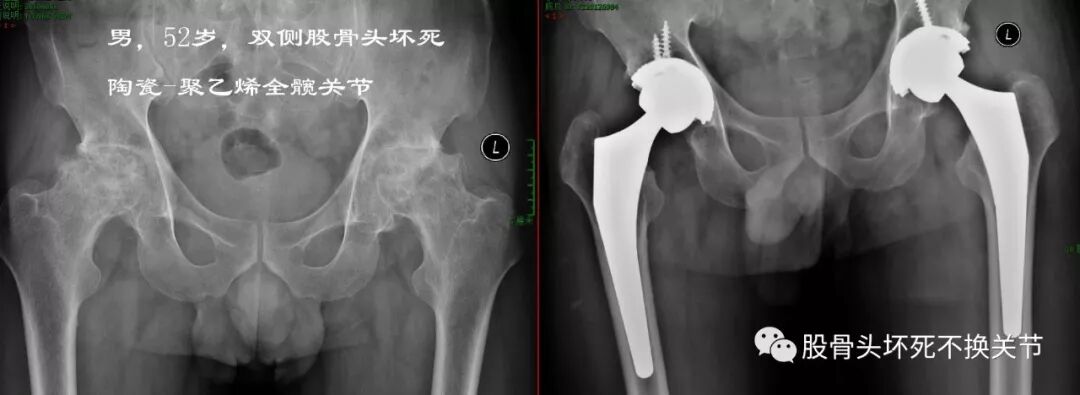

52岁,陶瓷对聚乙烯双侧置换

陶-聚乙烯关节术后8年,未见明显磨损